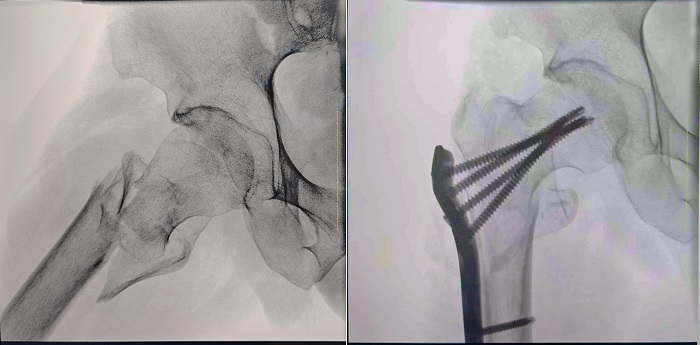

患者:70歲,男

臨床診斷:右股骨粗隆間骨折,伴有下肢位移、外旋

術式:右股骨粗隆間骨折切開復位內固定術

一體式移動C型臂拍攝的術前影像

大視野 高清成像 觀察更全面

普愛醫療一體式移動C型臂采用30CM×30CM的平板探測器,能夠幫助醫生全面觀察患者斷端分離錯位情況,確保手術方案的精準制定。